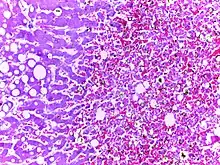

![]() | Congestive hepatopathy (CVC liver) | Micrograph showing chronic venous congestion of liver | Category: Histopathology of chronic venous congestion of liver | Congestive hepatopathy of liver |